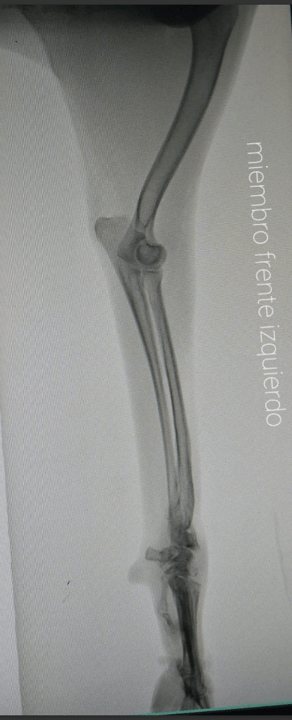

Trixie gets deeply stressed around vets and is always initially nervous of strange men, so it wasn’t a nice experience for her, our stress levels were on par! Then we got the results. Her x-ray images shocked our rescue vet and Dr Pam. Trixie had fractures in her remaining front leg and her left hip that had healed badly. Here are a few of the images:

Thanks for the images; this poor dog! She has a pretty bad pelvic fracture on the right side so her hip joint is not normal. The left hip looks okay and her elbow joint is normal but unfortunately her carpus (wrist) joint is out of place. Most likely the tendon damage pulled the joint apart or she suffered a fracture through the joint plate but either way her joint is not lined up so she is unable to bear weight. Combine that with the fractured pelvis and amputated leg and I am surprised that this girl can even get up.

In a perfect world she would have a carpal arthrodesis where they fuse the joint with a metal plate but that might not be something you can find; even here in the States that surgery is generally only done by a specialist. I would look into getting a carpal brace preferable a heavy duty one. You can order those through Hero braces or OrthoPet but your vet might need to help you take measurements. You will want a brace that is hinged and has heavier material such as fiberglass or multiple soft layers with padding. You can try to pad and wrap the area yourself or with your vet but you need to make sure it is not too tight and that you do not create any pressure sores.